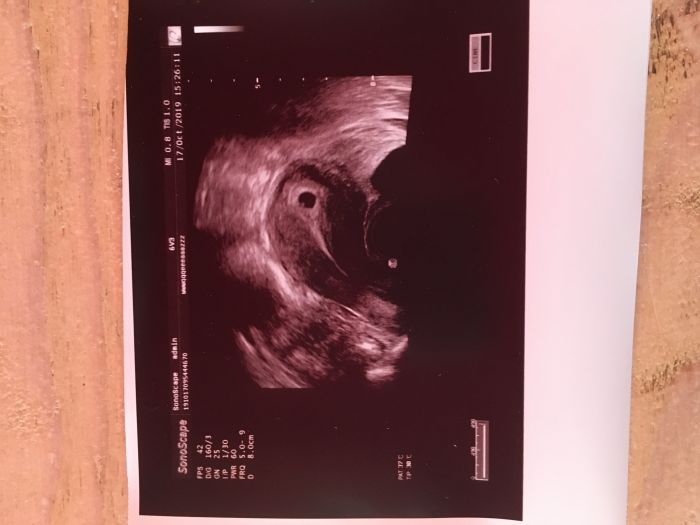

[1131323] vítejt mezi nama a držím moc palečky ať to dopadne dobre...ja byla u doktora dnes a dělal mi utz tak mám fotecku odpovídá 5+5 a mám přijít za 14 dni

Ahoj holky, dneska jsem byla tedy na kontrole a termín mam 6.6. 2020. Všechno je zatím v pořádku tak jsem ráda. Podle utz to vypadá na 7+2 momentálně. Akorát jsem myslela, že tam dneska ani nedojedu, během dopoledne jsem třikrát zvracela a celkově mi je pořad tak nějak špatně. Tak snad to poleví, všem držím palečky na kontrolách :)

Bejly a FRox gratuluji ke krásným snímkům a potvrzení od dr